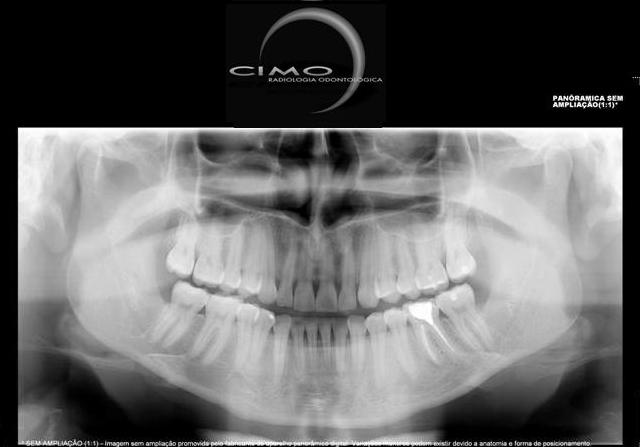

PANORÂMICA DIGITAL

Também chamada de ortopantomográfica.

Permite em uma única tomada, a visualização das estruturas do complexo maxilo-facial, conferindo portanto sua utilidade em todas as especialidades. Devido ao posicionamento do paciente (afastado do filme) a imagem não possui a mesma riqueza de detalhes finos como na periapical, porém vantagens como ampla cobertura da área examinada, a projeção das estruturas anatômicas com reduzida superposição, além da baixa dose de radiação, são justificativa de sua crescente aceitação.